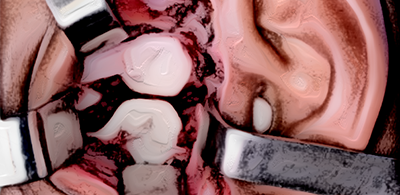

Dor Orofacial e

Disfunção da Articulação Temporomandibular (ATM)

Reconstrução da ATM sem uso de próteses metálicas